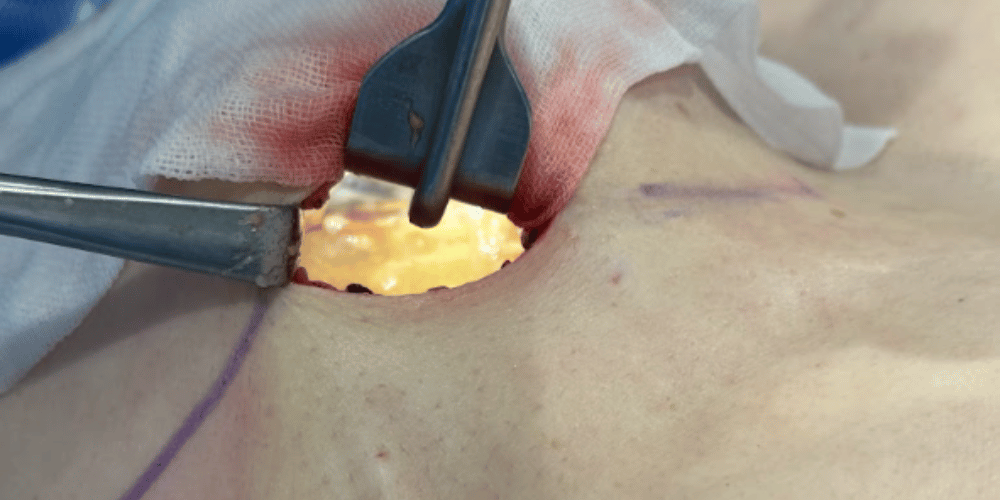

「完全直視下法」へのこだわり

他院で行われる「吸引法(注射器で吸う)」では、組織にこびりついたジェルや被膜は取り切れません。当院では直視下で確実に処理します。

完全直視下法イメージ

見る

小さな切開から内部を直接目視し、ジェルの位置を特定。

プロセス:見る